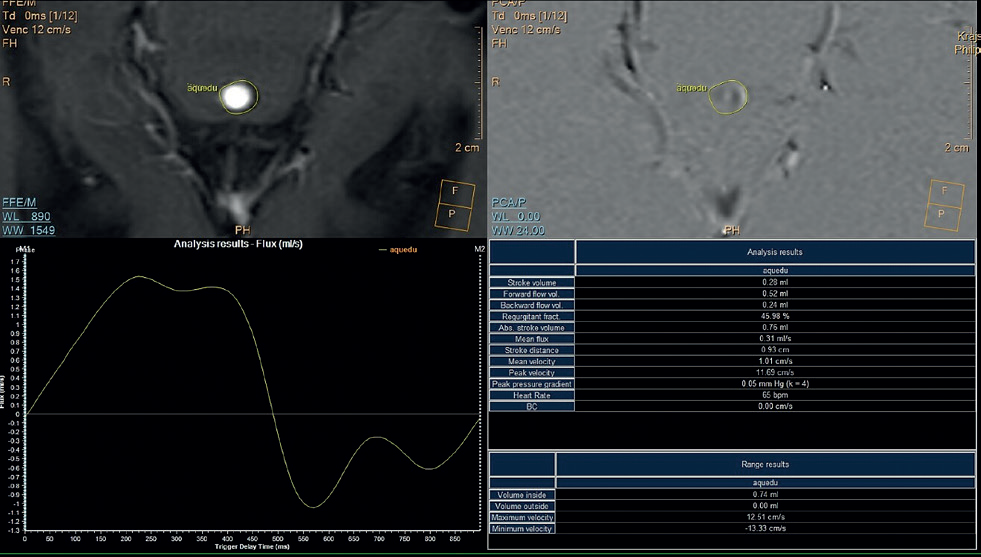

V naší kazuistice hraje ústřední roli patnáctiletá dívka, která byla sledována dětskou neuroložkou pro měsíce trvající silné bolesti hlavy. Tyto byly lokalizovány do oboustranných spánkových oblastí bez návaznosti na specifické činnosti, polohu či jiné faktory. Bolesti byly přítomny denně, dívka často vynechávala ve škole, kde se i beztak její prospěch horšil kvůli poruše pozornosti a paměti. Ošetřující neuroložka indikovala magnetickou rezonanci (MR) mozku, kde byla nalezena dilatace komorového systému (obr. 1). S tímto byla pacientka přijata do naší péče. V anamnéze nebyly vystopovány žádné rizikové faktory pro vznik hydrocefalu – perinatální anamnéza byla negativní, pacientka neprodělala žádný neuroinfekt či úraz hlavy. Na MR mozku byla viditelná výrazná dilatace komorového systému, zejména supratentoriálně, nicméně ani IV. komora nebyla fyziologické šíře. Dále bylo nápadné zúžení vtokové části aquaeductus mesencephali s velmi výrazným tokovým artefaktem na PSIF, tedy sekvenci určené k detekci toku likvoru (obr. 2), obraz zúžení mokovodu s hyperdynamickým tokem likvoru. To podporoval i výrazný bowing III. komory, tedy vyboulení III. komory a vyhlazování jejích výklenků, turecké sedlo však nebylo zvětšeno ani nikterak destruováno (obr. 3). Po příjmu pacientky byla provedena optická koherentní tomografie (OCT) zrakového nervu, která edém terče zrakového nervu neprokázala. Vzhledem k tomu, že se nejednalo o jasný obstrukční hydrocefalus, byla následně provedena lumbální punkce ke změření tlaku likvoru a odběru jeho vzorku k laboratorní analýze. Tlak byl v normě – 17 cm H20, v laboratorních vyšetřeních odchylka též nebyla nalezena. To znamená, že na MR mozku jsou jasné známky hydrocefalu, ale jak nález na očním pozadí, tak i lumbální punkce ukazují na normální tlak mozkomíšního moku. Vzhledem ke zmíněnému výraznému tokovému artefaktu likvoru přes aquaeductus mesencephali jsme se zaměřili na tento fenomén. Provedli jsme MR mozku metodou fázového kontrastu (Phase‑Contrast MRI, PC‑MRI), která umožňuje tokové parametry likvoru kvantifikovat. Opravdu se potvrdilo, že tok likvoru je hyperdynamický, maximální systolická rychlost byla 11,7 cm/s (obr. 4). Byla tedy vyslovena hypotéza, že se jedná o stenózu mokovodu a pacientce, a vzhledem k věku samozřejmě i rodině, byla navržena endoskopická stomie III. komory (ETV). Vzhledem k absenci mechanické obstrukce mokovodu při současně vysokých systolických rychlostech průtoku likvoru přes mokovod byla vyslovena hypotéza, že se jedná o funkční stenózu mokovodu. S přihlédnutím k věku pacientky byly ona i její rodina seznámeny s možností miniinvazivního výkonu ve smyslu endoskopické stomie III. komory (ETV). Rodina byla však k operaci rezervovaná, proto jsme nabídli tehdy novou diagnostickou metodu – miniinvazivní přímé měření intrakraniálního tlaku (ICP) čidlem s telemetrickým přenosem naměřených hodnot (Raumedic Neurovent‑P‑telâ). Hlavní výhodou této metody je možnost kontinuálního měření ICP i v domácím prostředí až po dobu 90 dnů. Implantace čidla byla provedena bez komplikace a pacientka byla edukována o způsobu monitorace ICP, zejména vedení deníku činností a bolestí hlavy. Po třítýdenním měření byla data analyzována a porovnána s deníkem. Byl nalezen jasný korelát mezi silnou cefaleou a hroty ICP až k hodnotám 30 mm Hg. Zvláště nápadné byly křivky během noci, kdy krátce po elevaci ICP byla pacientka bolestmi hlavy opakovaně vzbuzena. Po předložení výsledků této metody pacientka i rodina souhlasily s provedením ETV. Zákrok byl proveden bez komplikace, průchodnost stomie byla verifikována pooperačním vyšetřením pomocí MR mozku (obr. 5). Pooperačně se však symptomy pouze zmírnily a po pěti týdnech nastala kompletní recidiva obtíží. Byla vyslovena suspekce na okluzi stomie, nicméně kontrolní MR mozku toto nepotvrdila. Další postup mohl mít dva scénáře. První by znamenal připustit, že pacientčiny nespecifické symptomy nebyly dány porušenou likvorodynamikou a naše rozvaha byla chybná. Druhý by znamenal setrvání v našem předpokladu, že obtíže jsou spojeny s likvorodynamickými poměry, nicméně ETV nepostačovala k odvedení dostatečného objemu likvoru při jeho pulzatilním toku. Jedinou další léčebnou metodou by v tom případě bylo zavedení ventrikuloperitoneálního (VP) shuntu. Což je však další invazivní výkon, proto jsme uvažovali o další diagnostické metodě – lumbální drenáži. Jedná se ve své podstatě o simulaci zavedeného shuntu dočasnou drenáží likvoru ze spinálního subarachnoidálního prostoru. Po domluvě s pacientkou a rodinou byla lumbální drenáž zavedena a ponechána tři dny s celkovým objemem odvedeného likvoru 500 ml. Po celou dobu drenáže byla pacientka zcela bez bolestí hlavy. Test byl tedy pozitivní. Po vytažení drenáže se bolesti vrátily do dvou dnů. Nyní jsme s větší jistotou mohli indikovat zavedení VP shuntu. Protože jsme předpokládali, že nastavení ventilu shuntu nebude u takto komplexního typu hydrocefalu jednoduché, zavedli jsme typ ventilu, který umožní regulaci tlaku separátně pro horizontální a vertikální polohu těla – Miethke proGAVâ 2.0 s iniciálním nastavením 10 cm H2O a m.Blueâ s nastavením 25 cm H2O (obr. 6). Operace proběhla bez komplikace a pacientka byla propuštěna do domácího ošetřování s tím, že případné změny nastavení ventilu budou provedeny v rámci ambulantních kontrol. Při první kontrole pacientka udávala přetrvávající bolesti hlavy, proto bylo nastavení ventilu proGAVâ 2.0 pro horizontální polohu sníženo na 5 cm H2O. Při další kontrole za dva týdny pacientka popisovala kompletní vymizení původních příznaků vleže. Popisovala však symptomy předrénování, tedy výraznou cefaleu při vertikalizaci s rychlou úlevou v horizontální poloze. Proto bylo nastavení antigravitační jednotky m.Blueâ postupně zvýšeno až na maximum, tedy 40 cm H2O. Na tomto nastavení byla nalezena rovnováha mezi potřebou nízkoodporové drenáže likvoru vleže a zamezení předrénování sifonovým mechanismem vstoje. Pacientka je nyní sledována po operaci jeden rok, je zcela bez bolestí hlavy.

Samozřejmě základní vyšetřovací metodou je neurologické vyšetření. Existují typické příznaky hydrocefalu, nicméně bolest hlavy je symptomem velice nespecifickým a jako takový příznak nevede k diagnóze. Druhým základním vyšetřením je zobrazení mozku. Jako první radiologická metoda je využívána výpočetní tomografie (CT) mozku. Jedná se ale o vyšetření zatížené rentgenovým zářením a dokáže zobrazit jen hrubé změny v anatomii komorového systému. Optimální je proto MR mozku s možností detailního zobrazení a posouzení i funkčních parametrů. U naší pacientky byl na MR na T2 váženém obraze nápadný výrazný tokový artefakt v aquaeductus mesencephali. Jeho posouzení je ale čistě subjektivní, proto byla později použita k přesné kvantifikaci tokových parametrů likvoru metoda PC‑MRI, která prokázala hyperdynamický tok likvoru. Pouhá dilatace komorového systému s nálezem hyperdynamického toku likvoru ale neznamená automaticky zvýšený intrakraniální tlak. Proto jsou důležité další zpřesňující testy, které jsou ale zatíženy jistou invazivitou. Nejméně invazivní metodou je lumbální punkce. Ta je sice u obstrukce kontraindikovaná, v našem případě však byla stenóza aquaeductus mesencephali inkompletní, bez mechanické obstrukce, proto mohla být punkce provedena. Byla primárně indikována ošetřujícím neurologem k odběru vzorku likvoru v rámci diferenciální diagnostiky. Zvýšený tlak likvoru při lumbální punkci naměřen nebyl. U tohoto typu hydrocefalu však tlak ve spinálním subarachnoidálním prostoru nemusí mít vypovídající hodnotu – ke kongesci likvoru dochází supratentoriálně. Další diagnostické metody s sebou nesou vyšší invazivitu, proto jsme vzhledem k nálezu na MR mozku navrhli ETV. Tato operace je založena na provedení stomie dna III. komory. Tím se vytvoří další odtoková cesta likvoru do subarachnoidálních prostor. Vzhledem k tomu, že jsme nemohli zaručit jistý efekt, nebylo toto rodinou akceptováno. Ke zpřesnění diagnózy jsme tedy použili implantaci čidla k přímému měření supratentoriálního tlaku Raumedic Neurovent‑P‑telâ s telemetrickým přenosem naměřených hodnot. Jedná se o čidlo implantované přímo do mozkové tkáně o délce 25 mm a šířce 1,76 mm. Postačí tedy velmi malý trepanační otvor. Čidlo je implantováno subgaleálně a kožní kryt je celistvý, nehrozí tedy infekční komplikace a měření může probíhat až 90 dnů. Při analýze dat jsme zjistili korelaci s nadlimitními hodnotami ICP a vyššími amplitudami pulzací s bolestmi hlavy. Poté rodina dala svolení k ETV. Endoskopický zákrok byl proveden bez komplikace. Pro tyto jednoduché ventrikulostomie využíváme PaediScopeâ. Jeho výhodou je tenký průměr (3 mm) a riziko operace se tak minimalizuje. Provedený výkon však nevedl ke zmírnění příznaků. Naše hypotéza tohoto neúspěchu byla, že zúžení mokovodu nebylo jen morfologické, ale i funkční – dané vyšší pulzní amplitudou likvoru. Mokovod byl tak příliš úzký pro odvedení systolických vln likvoru a ani stomie ve III. komoře k dostatečnému odtoku likvoru nevedla. Další možnou metodou léčby hydrocefalu je zavedení ventrikulo‑peritoneálního shuntu. Jedná se však o trvalé zavedení katétrů s rizikem infekce. Abychom měli jistotu, že bude implantace shuntu efektivní, rozhodli jsme se zavést lumbální drenáž. Ta je založena na dočasném odvedení mozkomíšního moku katétrem ze spinálního subarachnoidálního prostoru do sběrného vaku. Tím simulujeme poměry s implantovaným shuntem. U tohoto typu hydrocefalu jsou sice důležité likvorodynamické poměry supratentoriálně, ale lze předpokládat, že dlouhodobá drenáž spinálního kompartmentu vede ke snížení tlaku a pulzací likvoru i intrakraniálně. Po dobu drenáže byla pacientka opravdu bez příznaků a mohli jsme tedy s vyšší mírou jistoty implantovat shunt (obr. 7). Pro regulaci tlaku jsme použili kombinaci ventilů Miethke proGAVâ 2.0 a Miethke m.Blueâ. Tato sestava ventilů umožňuje regulovat tlak likvoru odděleně pro horizontální a vertikální polohu těla. U tohoto typu hydrocefalu je totiž důležité, aby byly pulzní vlny likvoru drénovány katétrem s nízkou rezistencí. K tomu je zapotřebí nastavení systému na nízkou hodnotu. To by samo o sobě vedlo ve vertikální poloze k předrénování. Proto byl implantován i ventil k regulaci tlaku při vertikalizaci. Aby vymizely příznaky předrénování, musel být nastaven na maximální hodnotu. Bez této možnosti by musel být k zamezení předrénování nastaven vyšší tlak i pro horizontálu, a i tato léčebná metoda by selhala.